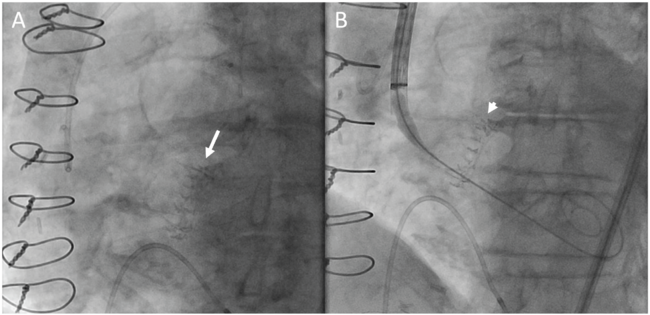

During the TAVR procedure, coplanar angle estimated from preoperative CT scan was easily adjusted referencing the line of Cor-Knot in her aortic annulus without administrating contrast although poor radiodensity from the Trifecta valve. In the coplanar view, the TAVR valve depth was well appreciated in reference to the Cor-Knot line and the TAVR valve was deployed under controlled pacing without contrast use (Figure 1 and Figure 2). We achieved mean aortic pressure gradient of 9 mm Hg without perivalvular leakage or conduction abnormalities. She was discharged to home the next day without renal injury.